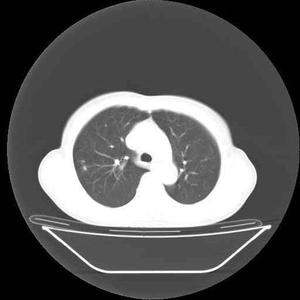

X线检查不但可早期发现肺结核,而且可对病灶部位、范围、性质。发展情况和治疗效果作出判断。X线表现有浸润、干酪样变和空洞形成,均属于活动性病变。活动性肺结核痰中常可找到结核菌。条索状、结节状病变经过一定时期观察稳定不变或已纤维硬结、痰培养结核杆菌阴性者,属于非活动性病灶。结核菌素试验呈强阳性者,常提示体内有活动性病灶,红细胞沉降率也可增快。